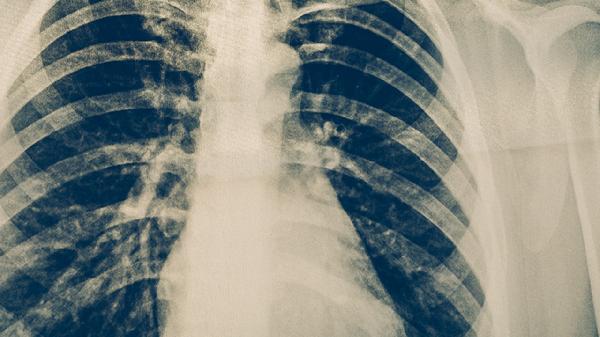

持续咳嗽咳痰超过2周、低热盗汗需警惕结核感染。胸部X线片和痰涂片检查是主要诊断手段。确诊患者需规范服用利福平胶囊、吡嗪酰胺片等药物6-8个月,接触者应进行预防性筛查。